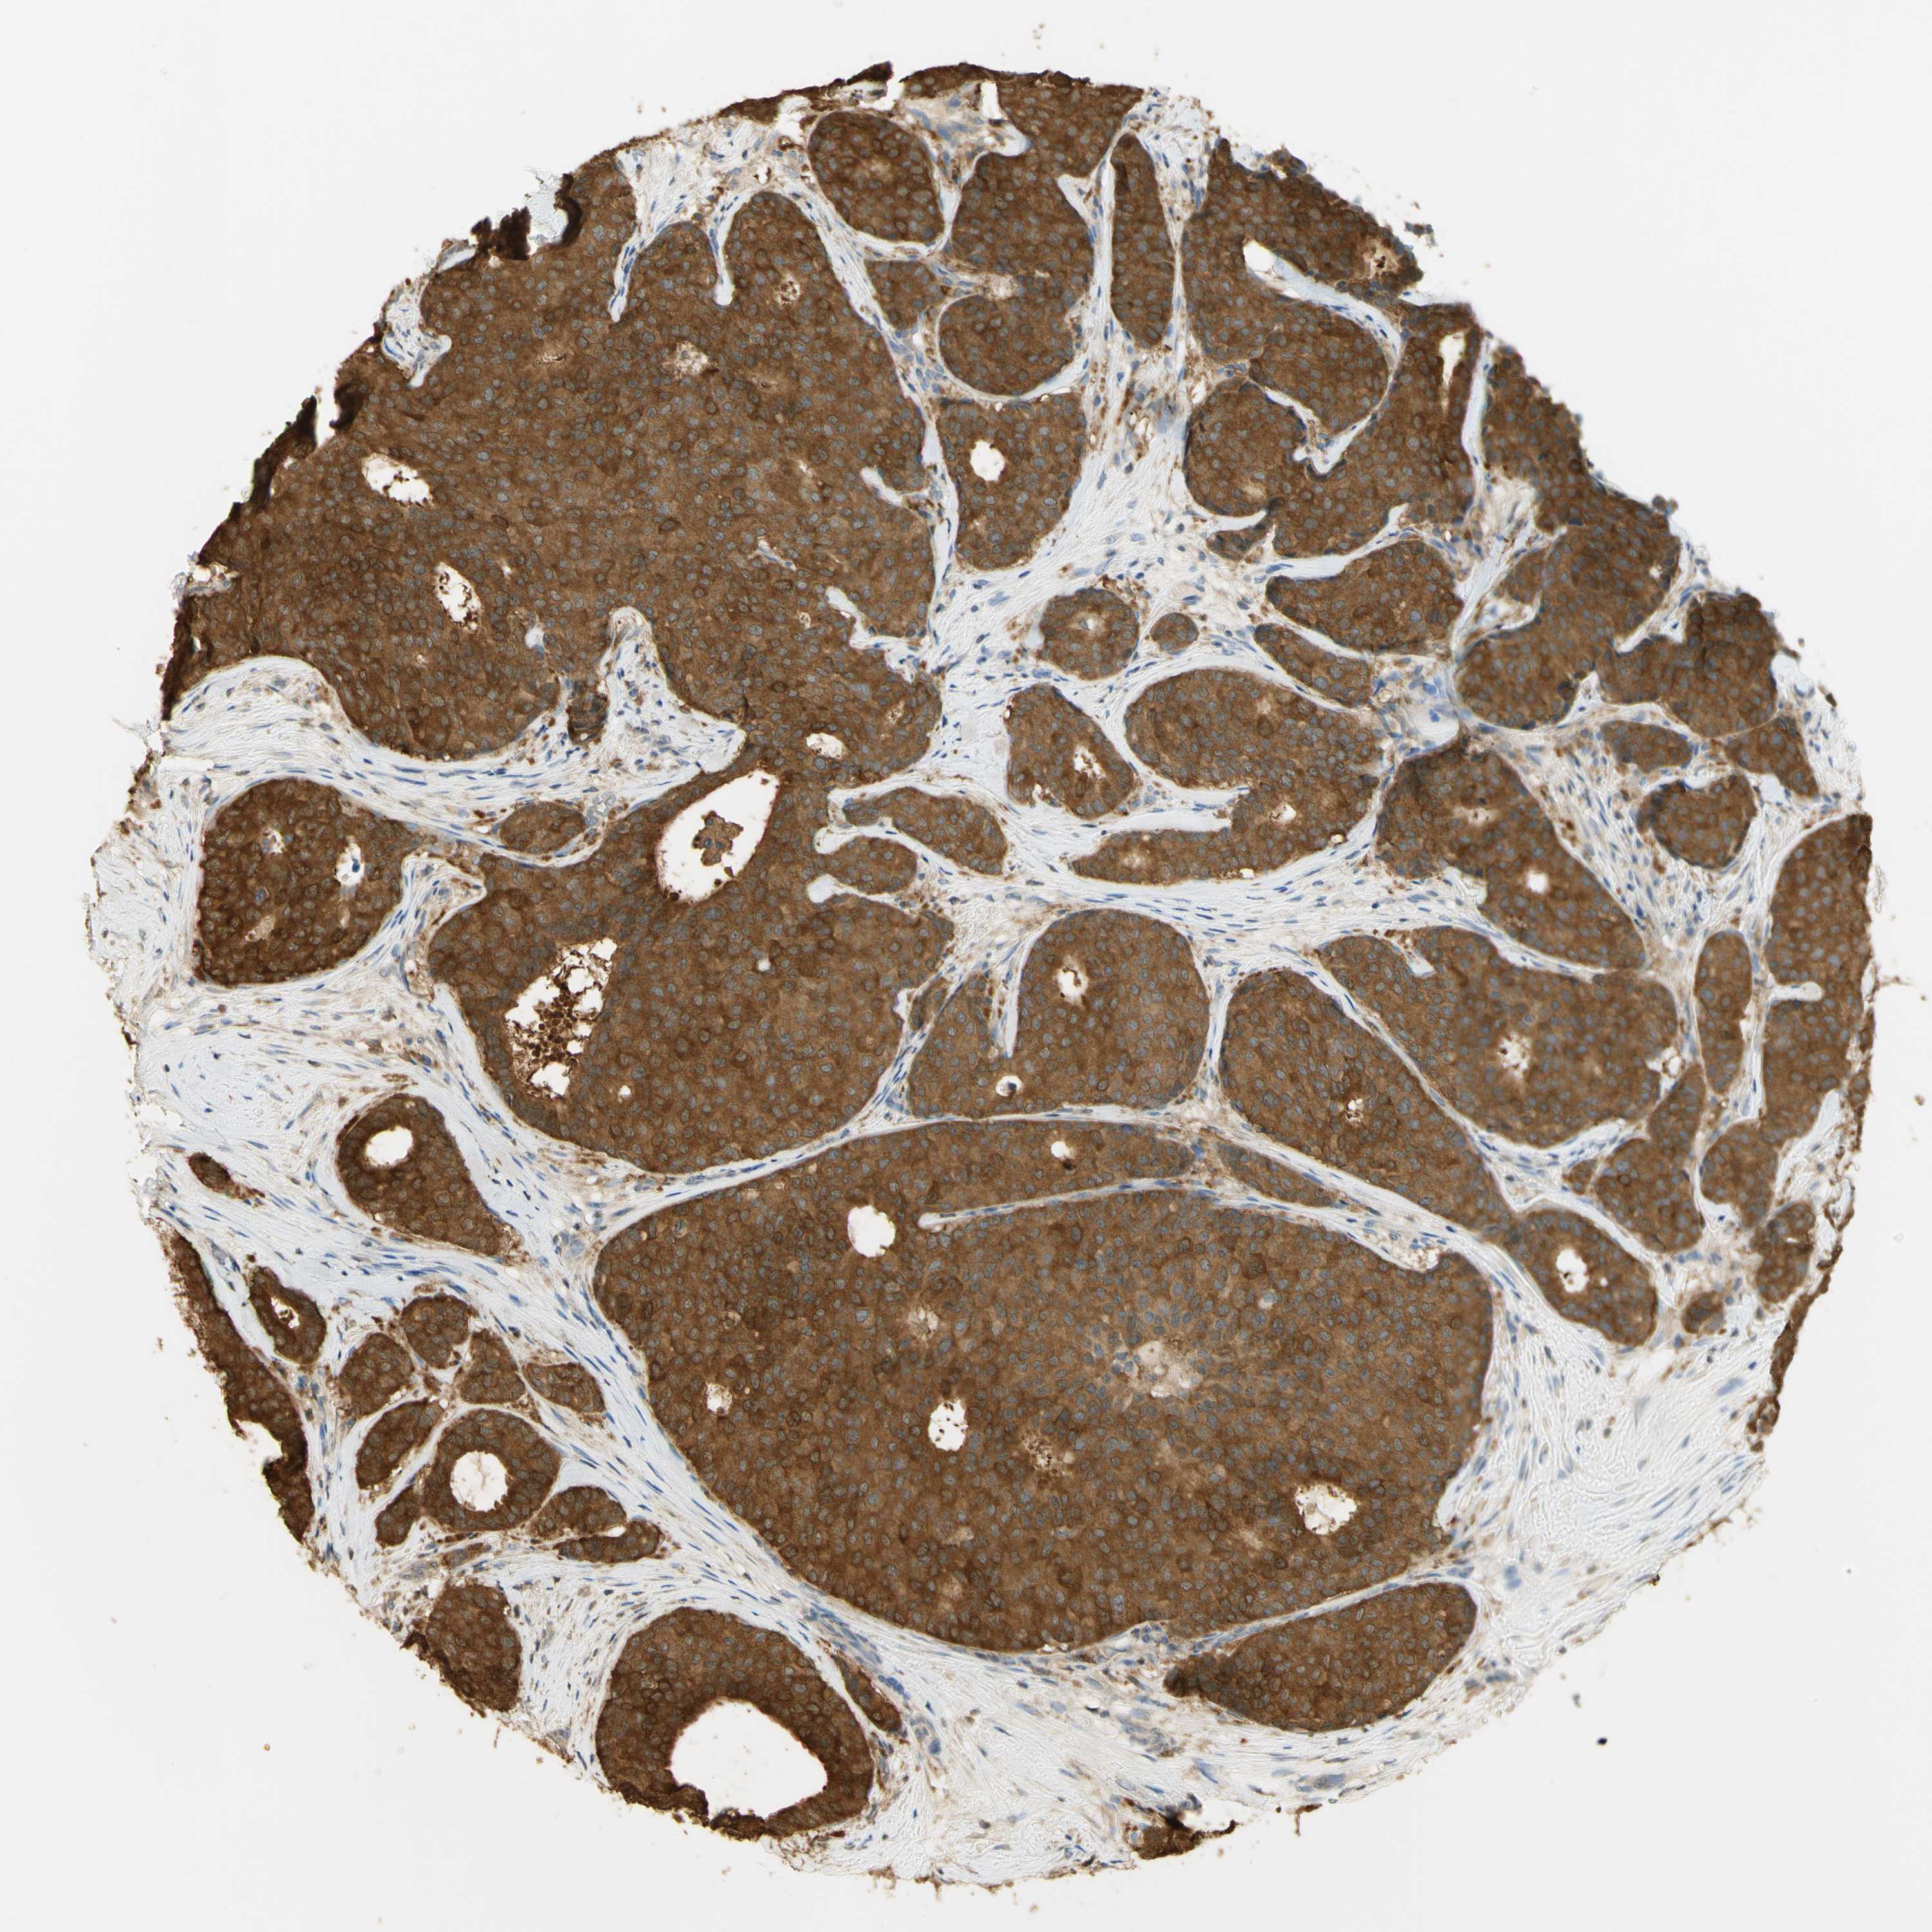

BRCA TCGA BRCA VALIDATION PROTEIN EXPRESSION